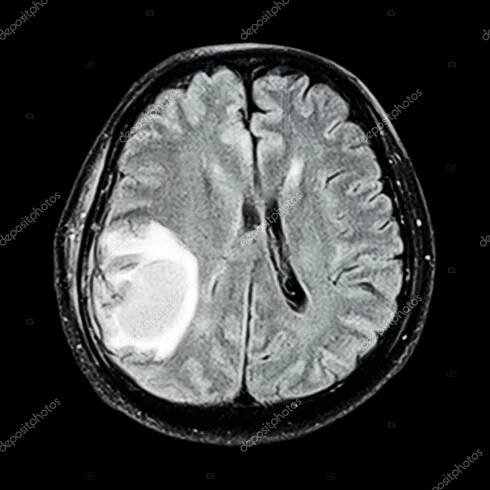

Nádor roste velmi pomalu, proto pacienti většinou přichází s velkým nádorem, který se projevuje tlakem na mozkovou tkáň. Někdy může být prvním příznakem epileptický záchvat, jindy je to vznik neurologických příznaků (částečné ochrnutí jedné…